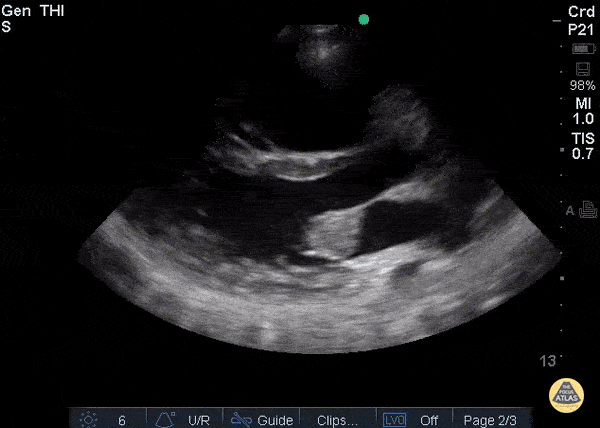

Valvulopathy - Endocarditis PLAX

Patient with history of IV drug use, admitted for sepsis. Parasternal long axis view shows large mass attached to anterior leaflet of mitral valve. Blood cultures prove bacterial endocarditis. Ria Dancel, MD. University of North Carolina at Chapel Hill